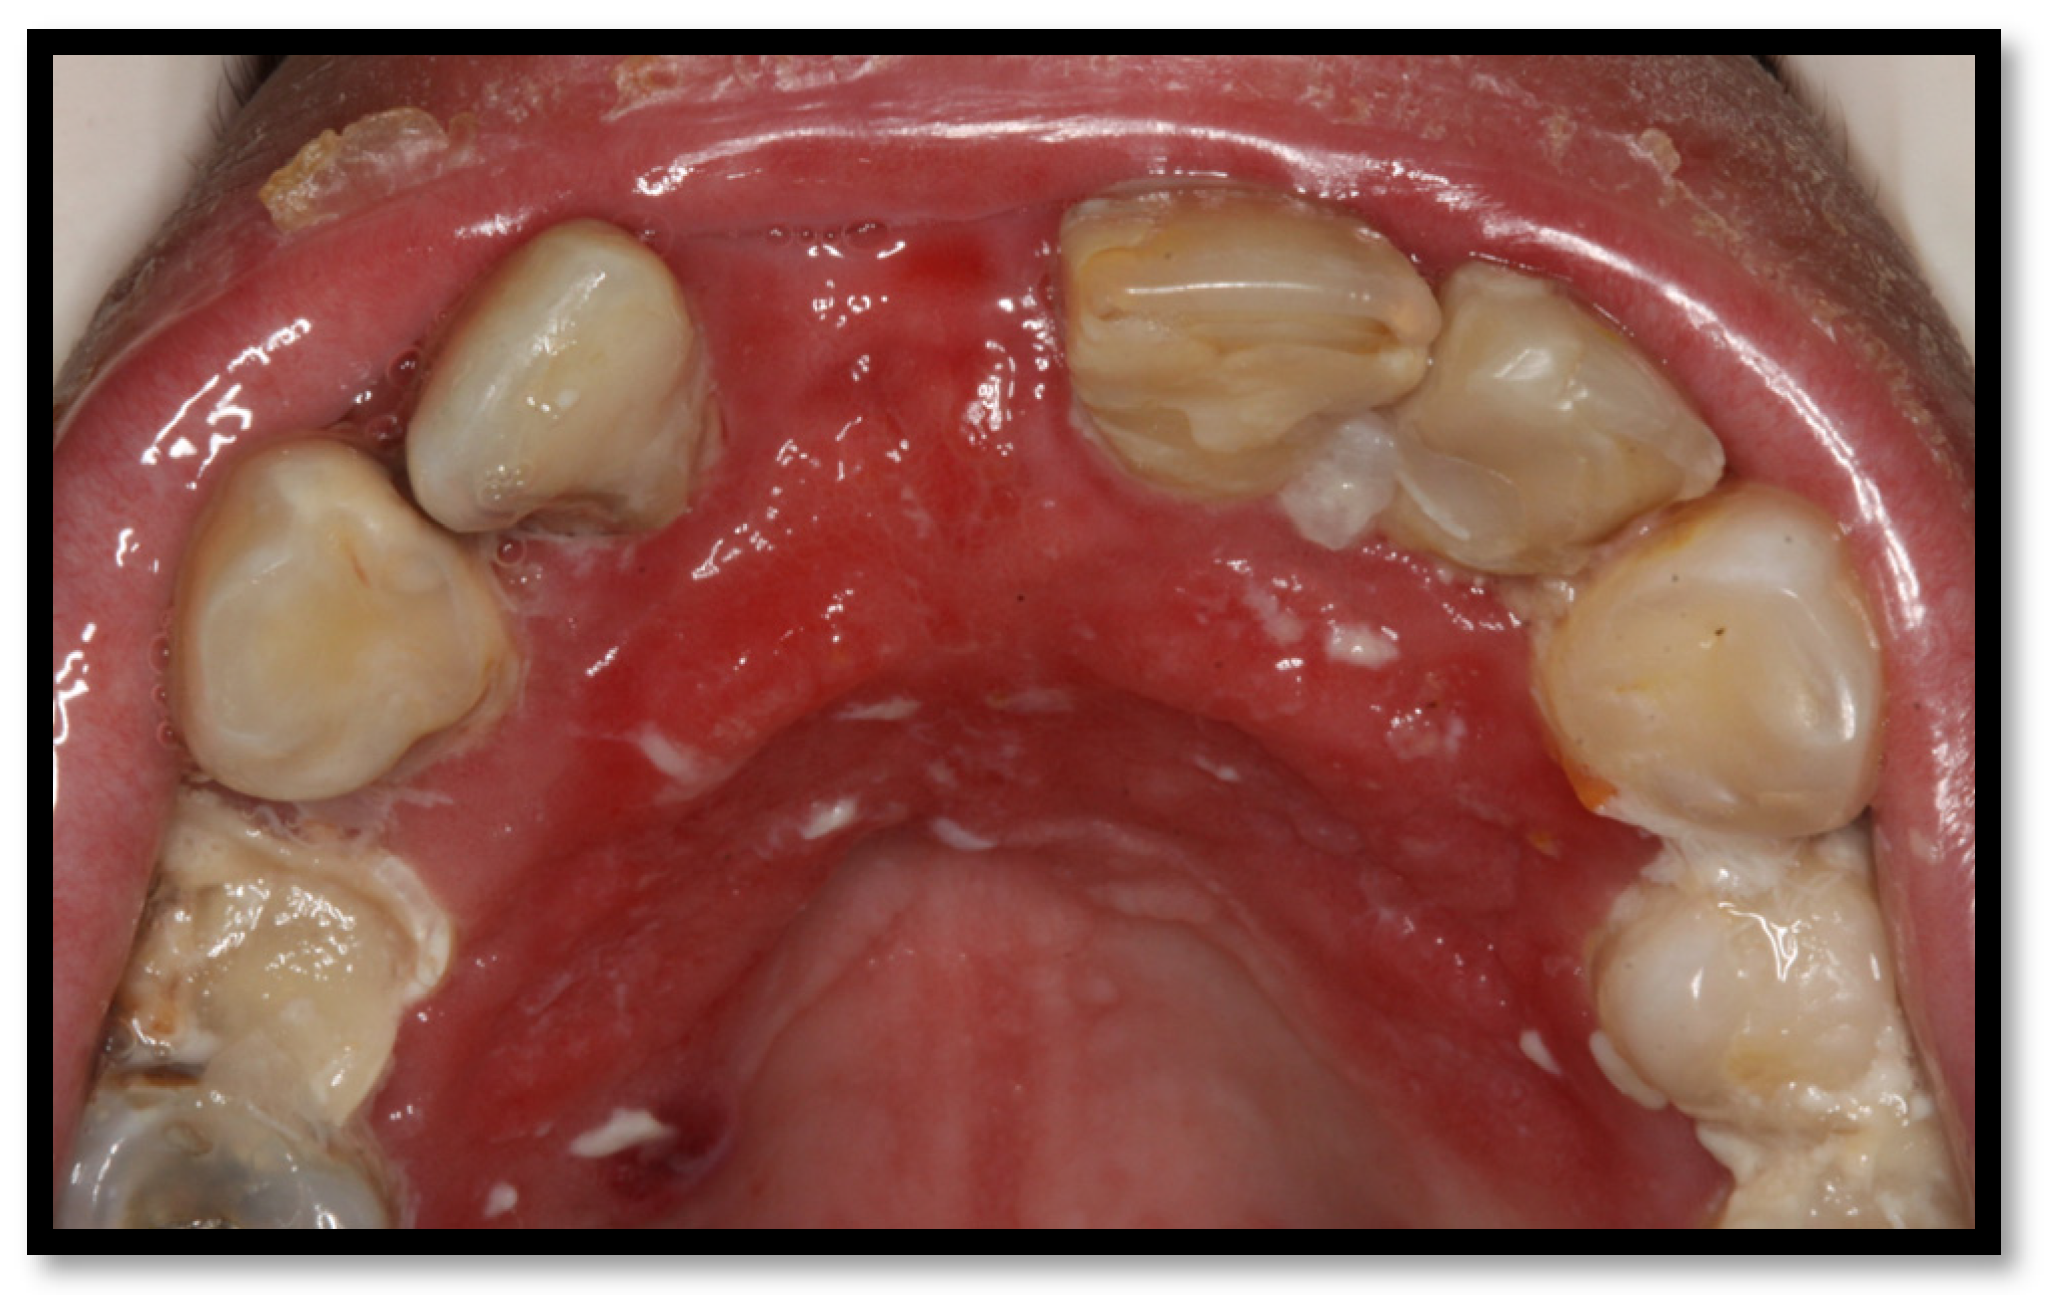

3.1. Linear Gingival Erythema

This condition is considered a form of gingivitis, which is clinically composed of a 2–3 mm erythematous streak along the gingival frame. It is commonly accompanied by diffuse red lesions or petechiae-like wounds scattered towards the apex of gums as well as the alveolar mucous membrane (Figure 4a,b). It usually appears along the anterior teeth, though being capable of growing towards the molars, altogether with mucosal bleeding and scarce dental biofilm [4,23,26]. Among the representative features of this injury are clinical insertion loss and the absence of ulcers or pain. Multiple Candida spp. have been associated with triggering this condition [16,23,26].

Figure 4.

(a) Linear gingival erythema in the anterosuperior area (b) linear gingival erythema in the anteroinferior area.